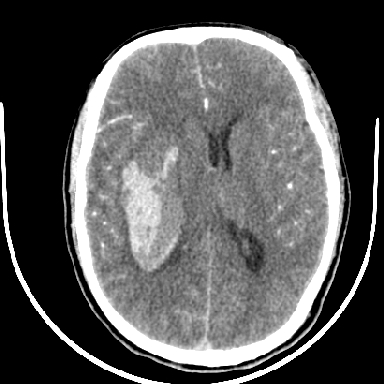

标题: CT6056:脑出血(血管畸形?) [打印本页]

标题: CT6056:脑出血(血管畸形?)

m 40突发头痛左侧偏瘫3小时

考虑高血压性脑出血,依据:

1是高血压性脑出血的好发部位,形态呈肾形,是高血压性脑出血的常见形状

2增强时占位效应加重了,考虑出血还没有停止

3病灶周围水肿不是太厉害,一般肿瘤出血水肿多非常明显

4病灶周围的‘软组织’影没有明显的强化

5至于脑血管畸形引起的出血,暂时没有看到明显的畸形血管影,也不太支持

支持右侧基底节脑出血

右侧基底节区脑出血.

支持右侧基底节区(主要为外囊区)原发性脑出血。

另附部分资料:“血液溢出血管外形成血肿,其内含有大量血红蛋白、血浆白蛋白,球蛋白,因这些蛋白对x线的吸收系数高于脑质,故ct呈现高密度阴影,ct值达40~90h,最初高密度灶呈非均匀一致性,中心密度更高,新鲜出血灶边缘不清。基底节区血肿多为“肾”型,内侧凹陷,外侧膨隆,因外侧裂阻力较小,故向外凸,其它部位血肿多呈尖圆形或不规则形”

术中抽出40ml陈旧血液,血肿底部似见一条索血管影